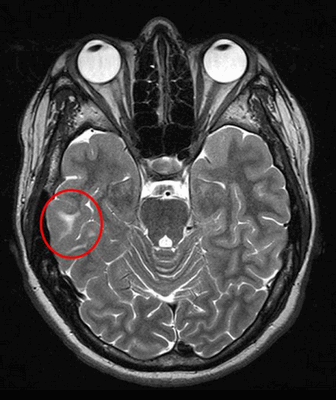

Красным кругом на МРТ головного мозга выделена область туберозного склероза, провоцирующего припадки